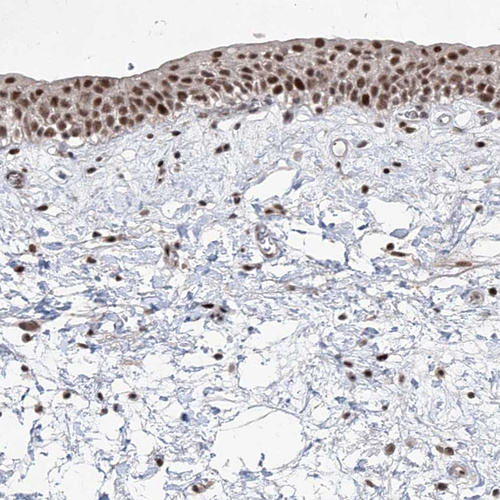

Immunohistochemical staining of human colon shows strong nuclear positivity in glandular cells.